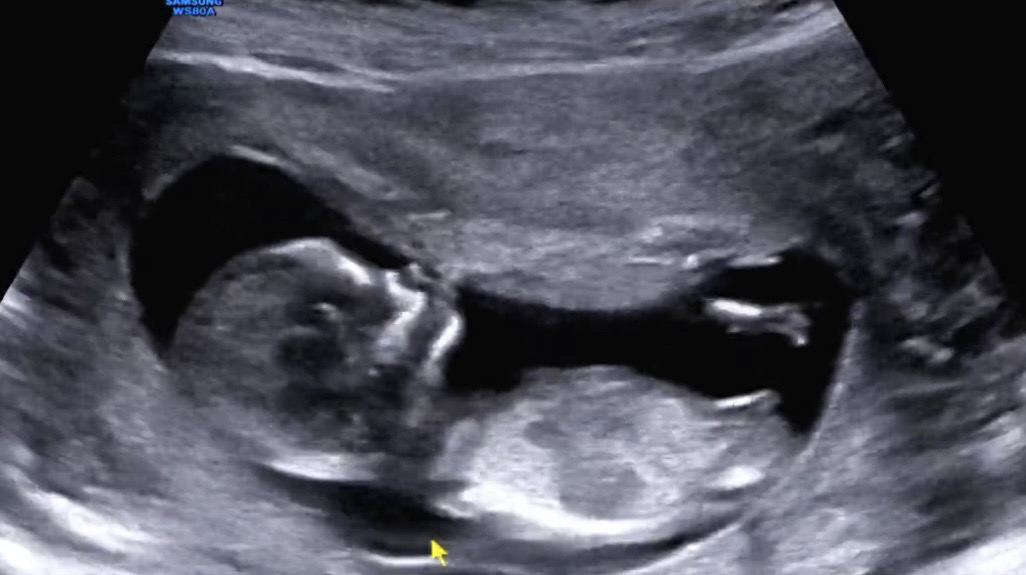

딸일까요 아들일까요? ㅠㅠ 저는 딸같은데.. 12주 5일입니다

저도 좀 끝이 들려보여서 아들일 거 같아요!

끝이 갈라져있지 않고 살짝 올라간것처럼 보여서 아들같습니다ㅋㅋ

딸같아용!